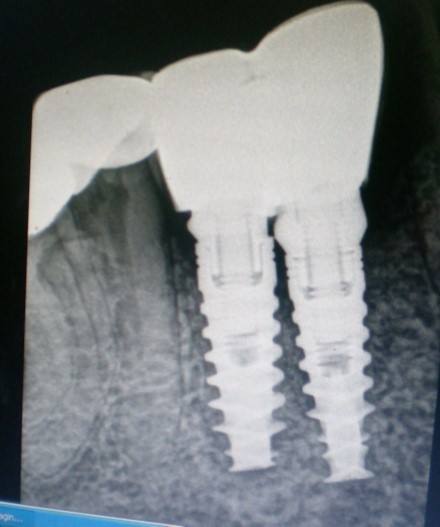

Unplanned implant placement or change in angulations of the implants due to anatomic limitations3,4 such as mandibular canal, mental foramen, nasal floor, sinus cavities or roots of the adjacent teeth, might result in close approximation of the implants (Figure 1), which poses tough challenges to the restorative dentist, who have to overcome certain technical difficulties for the fabrication of the prosthesis including making of a proper impression.

Figure 1.Radiograph – closely positioned implants.